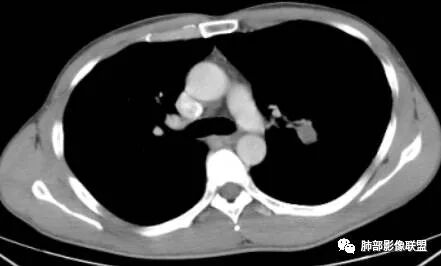

一切∮随缘:

左肺下叶肿块影平行支气管生长,边缘有纤维索条影,整体边缘平直,略彭隆,边界清楚,伴行支气管堵塞,周围伴有肺气肿,增强扫描强化不明显,无明显实性病变,考虑良性,支气管闭塞?支气管囊肿?平滑肌瘤。

小强:

左肺下叶孤立性肿块,形态规则,密度均匀,边界清,周围可以气肿及条索,无强化,左肺下叶后基底段支气管未见发育?考虑发育畸形,支气管囊肿 ?闭锁?先天性囊性腺瘤样畸形?

采莲:

老年女性,查体发现,左肺下叶不规则实性肿块,边缘平直收缩,无毛刺,周围有纤维牵拉及肺气肿,强化不明显。先天肺发育不良,支气管闭锁。

穿越七海的风:

左肺下叶扁平形结节,边缘光滑平直,边界清晰,周围肺气肿,强化不明显,支持先天肺发育不良,支气管囊肿

巴伟:

左肺下叶不规则高密度早灶,边缘平直为主,界清,周围有肺气肿,无强化,考虑良性病变,支持先天肺发育异常,支气管闭锁,鉴别支气管囊肿,囊腺瘤样畸形。

蔣勝華:

左肺下叶高密度,边缘光滑,周围肺气肿,强化不明显,ccam?鉴别 隔离

优彤:

左肺下叶肿块,边缘光滑,支气管动脉伴行,周围肺气肿,考虑支气管闭锁